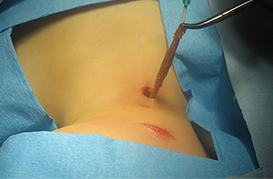

Cuerpo Extraño en Esofago